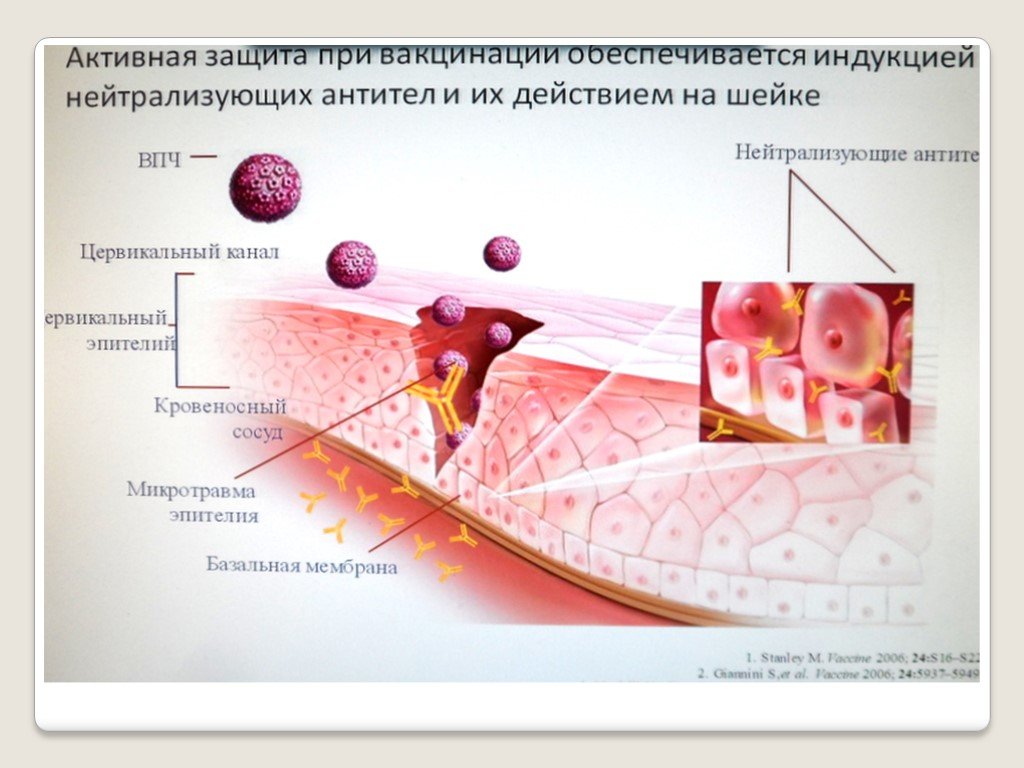

Факторы Риска ВПЧ: Визуальный Обзор и Информация